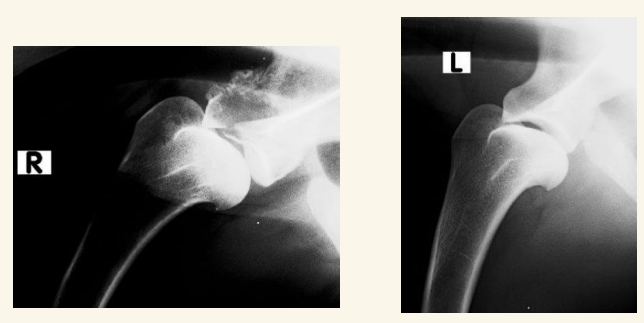

Luxación Coxo-femoral

- Por traumatismo, a veces leve si existe Displasia. Suele aparecer con fracturas de pelvis, uni o bilateral

- Normalmente cráneo-dorsal, aunque puede ser dorsal, ventral, caudal (rara) o intrapélvica

- Mejor 2 proyecciones pero en VD se ve mejor (ilion desplazado, mayor tamaño articular, perdida de contorno liso)

- Tambien hay luxacion sacro iliaca.

- Hay que ver la direccion de la luxacion. La mas frecuente es craneo-dorsal pero hay mas.